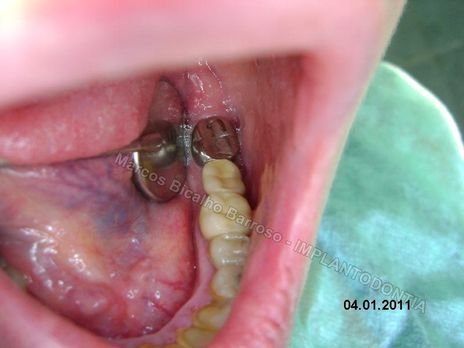

Paciente sexo feminino, 53 anos, queixava-se de dores ao mastigar com os dentes posteriores. No exame radiográfico percebi reabsorção radicular e lesão periodontal nos dentes 16,36 e 38 (os dois últimos, pilares de uma ponte-fixa 3 elementos). Ela estava de férias em minha cidade, com viagem marcada de volta para Curitiba 15 dias depois. Perguntou se era possível instalar os implantes e voltar para a sua cidade com os implantes e coroas instaladas. Meu planejamento foi instalar os implantes, se conseguisse um bom travamento primário, instalaria os provisórios 10 dias depois, no ato da remoção das suturas. Os cicatrizadores foram instalados imediatamente.

Fotos do caso